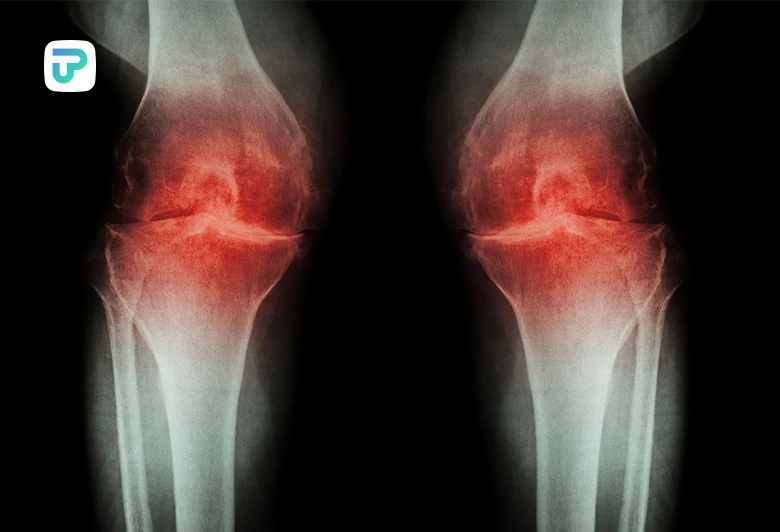

علت زانو درد هنگام نشستن و برخاستن به عوامل زیادی بستگی دارد. بر اساس تحقیقات، در حال حاضر 25درصد از افراد به دلیل درد زانو در مفاصل به این عارضه دچار هستند. دلایل گوناگونی برای زانو درد هنگام نشستن و برخاستن وجود دارد که نداشتن تحرک کافی در طول روز یکی از این دلایل است.

انواع مختلفی آرترزو زانو وجود دارد که مفاصل زانو را تحت تاثیر قرار میدهند. استئوآرتریت و آرتریت روماتوئید دو مورد رایج آرتروز زانو هستند.

- استئوآرتریت به دلیل ساییدگی غضروف ایجاد میشود و بیشتر در افراد بالای 50 سال رخ میدهد. تشدید ساییدگی غضروف باعث زانو درد هنگام نشستن و برخاستن خواهد شد.